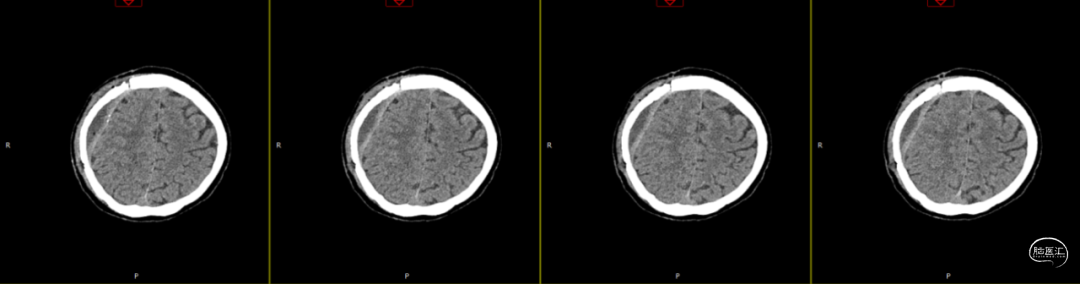

查体:嗜睡-昏睡状态,精神差,刺激睁眼,简单应答,肢体活动简单从嘱。GCS13分。双侧瞳孔等大等圆,直径2.5mm,对光反射灵敏,伸舌欠合作。转头、耸肩欠合作,四肢肌力4级,肌张力正常,颈抵抗(+),双Babinski sign未引出。枕部可见约5*4cm皮下血肿,压痛,拒按。周身多发片状皮肤擦伤。颅脑CT:双侧额叶脑挫裂伤;右侧顶颞枕部硬膜外、硬膜下血肿;蛛网膜下腔出血;右侧颞骨骨折累及右侧人字缝、顶乳缝,右侧顶乳缝旁小骨片;头皮软组织损伤、局部皮下血肿;双肺挫伤可能。

因患者在病情观察期间意识状态变差,昏睡-浅昏迷状态,予以急症手术治疗,清除硬膜外血肿,鉴于术中脑组织压力不高,予以骨瓣回置,术后严格控制血糖水平,常规使用抗生素(头孢唑林钠)预防感染。

术后第1天颅脑CT复查(如上图)